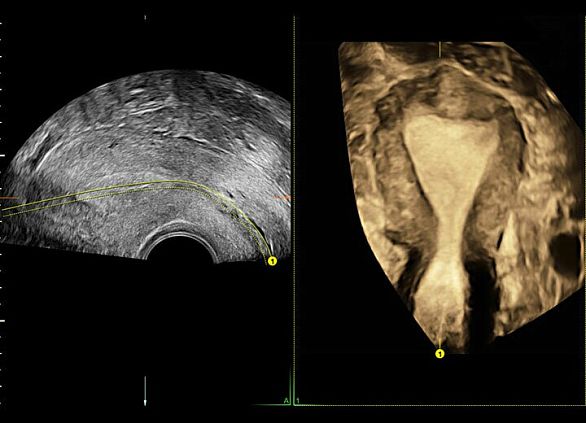

Клинические изображения

3D/4D УЗИ в ежедневной практике

Объемные ультразвуковые исследования являются неотъемлемым частью современной диагностики в сфере Женского здоровья. Благодаря передовым технологиям формирования УЗ луча и широким возможностям сканирования Voluson E6 обеспечивает получение 3D/4D изображений с исключительным анатомическим реализмом, что позволяет уверенно решать самые сложные клинические задачи.

- HDlive — технология формирования реалистичных ультразвуковых изображений. Она позволяет увеличить глубину восприятия, упрощая оценку анатомии и облегчая пространственное интерпретацию исследуемых структур, что придает уверенность в принятии клинических решений.

- SonoRenderlive — в зависимости от движений плода данная технология автоматически выбирает оптимальную плоскость для визуализации, позволяя существенно поднять эффективность получения объемных изображений.